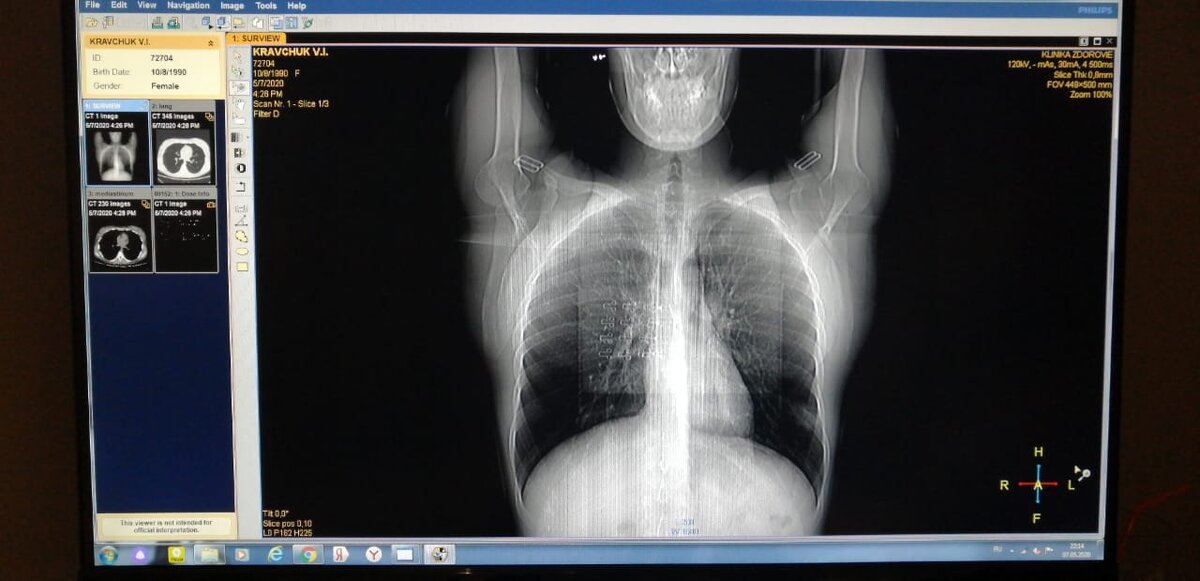

С горем пополам нашла. (-4.900₽)По диагнозу - левосторонняя пневмония 😷

Так как на нашу медицину надежды не было, то Мама в шахтах консультировалась с докторами и ещё друзья показывали мои снимки (где есть подозрение, что диагноз пневмония ошибочный 😬)